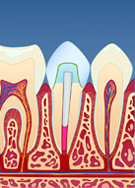

Dersom rotfyllingen vurderes og finnes tett og av god kvalitet, fjernes en del av rotfyllingsmassen for å gjøre plass til stiften (fig. II). Deretter kan stiften festes med en egnet sement (fig. III). Rundt stiften bygger man så opp en masse (konus) som slipes og formes til (fig. IV). Nå kan man ta avtrykk av den beslipte tannen, sende dette til en tanntekniker og få den ferdige kronen tilbake klar for sementering (fig. V og VI). Hele prosessen tar vanligvis 1 til 2 uker.

| figur II | | figur III | | figur IV | | figur V | | figur VI |